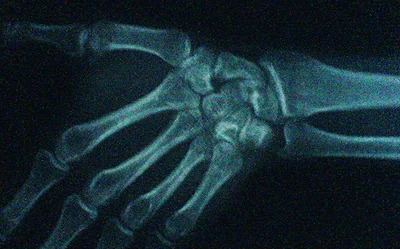

Adjunto documento gráfico no concluyente (lo sé):